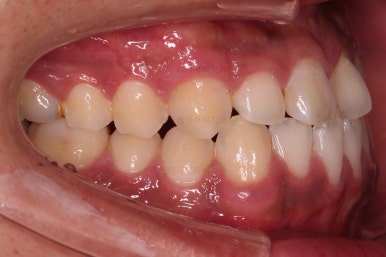

초진 시 입안의 모습입니다.

비교적 고른 편이긴 하나 아랫니가 전반적으로 밀려 나오면서 앞니끼리 부딪혀 있는 양상이고요.

어금니 맞물림도 긴밀하게 톱니바퀴처럼 위아래가 맞물려 있는게 아니라 엉성한 모습이죠.

앵글씨 3급 부정교합이라고 하는데요.